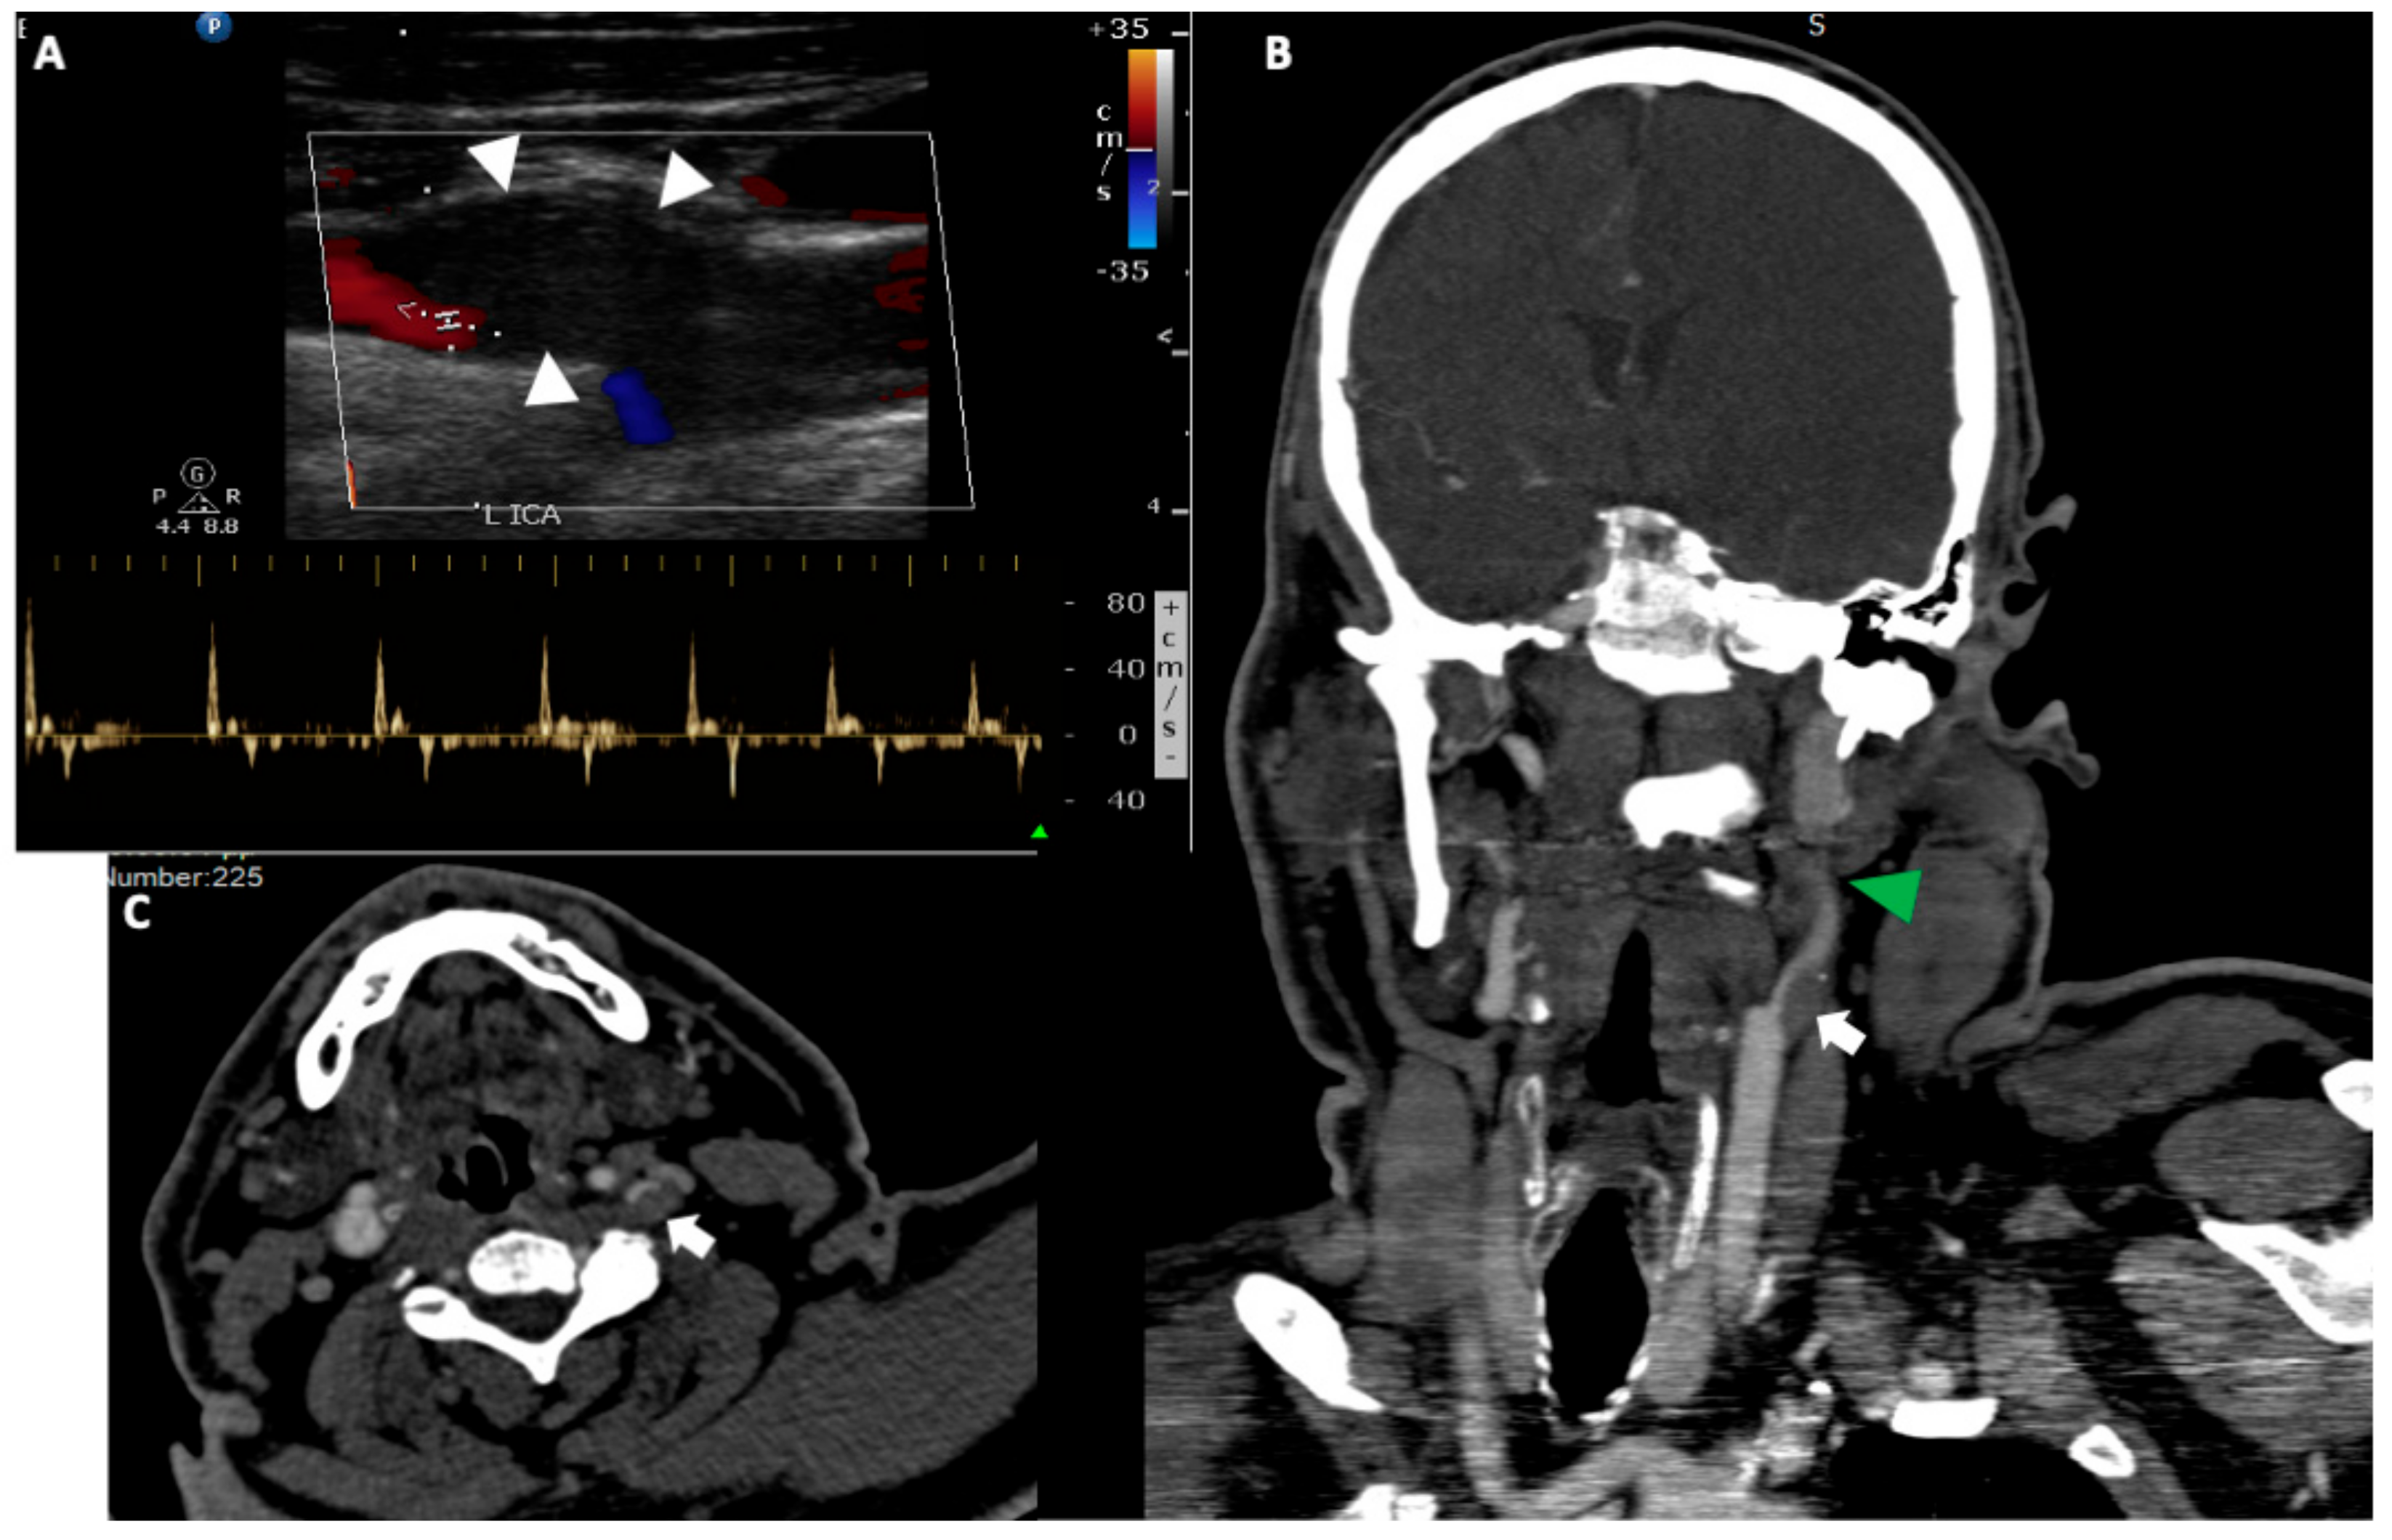

4.1. Dissection